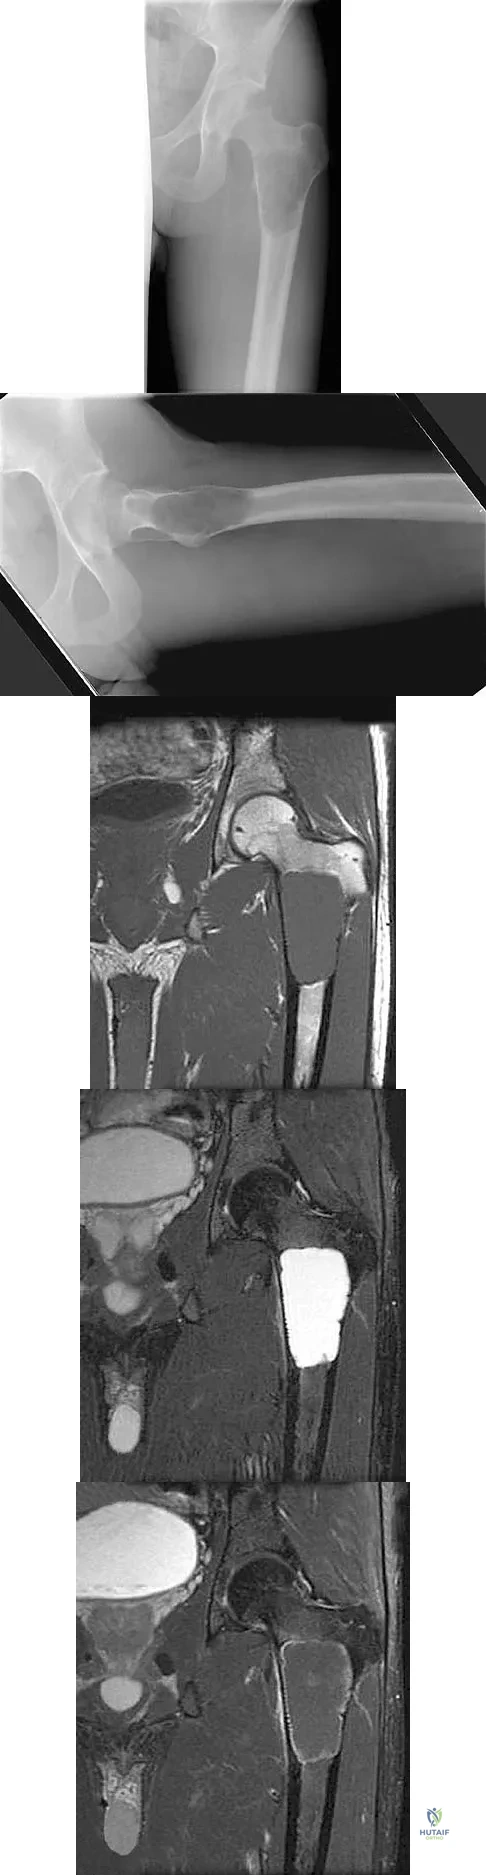

A 21-year-old man has mild but persistent aching pain in his left proximal thigh during impact loading activities. He denies pain at rest and has no other symptoms. Figures 34a through 34e show the radiographs and T1-weighted, T2-weighted, and gadolinium MRI scans of the left hip. What is the most likely diagnosis?

Explanation